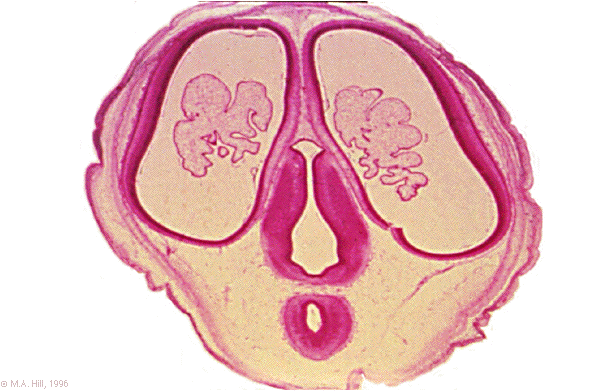

Hum A1